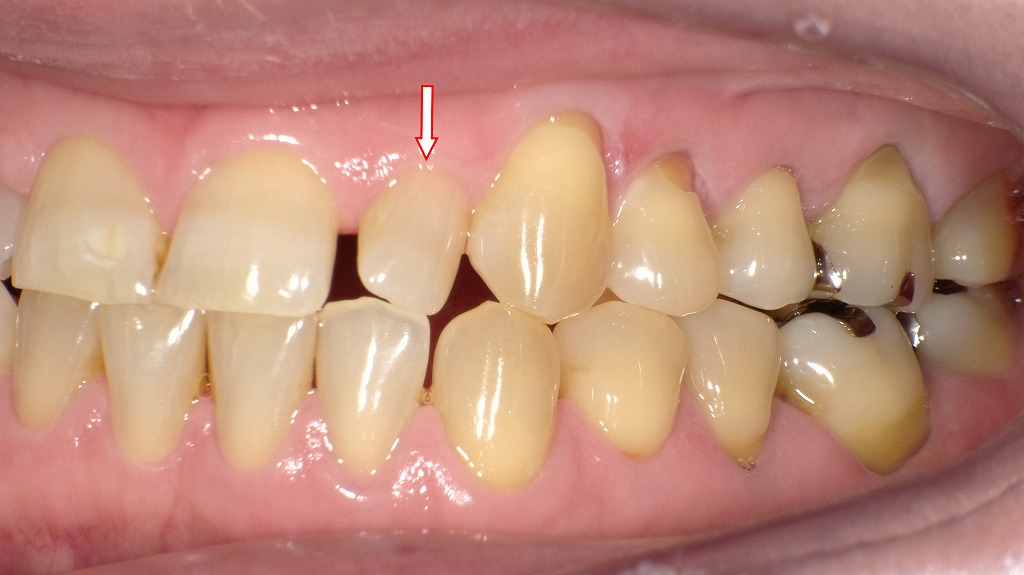

右側面観:歯が小さい症例

この画像は、同症例を右側方から撮影した口腔内写真です。赤い矢印で示されているのは、上顎右側側切歯(2番)の位置です。

■ 隣接歯との関係

小さな2番のため、

- 犬歯(3番)との間に**隙間(空隙)**が生じている

- 側切歯(2番)が著しく前方に傾斜している

といった歯列のアンバランスが生じています。

このような空隙は、歯並び全体のバランスや噛み合わせにも影響することがあります。